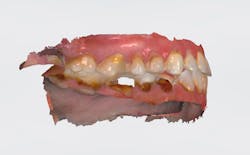

Case review: This 35-year-old female was diagnosed with Sjögren’s syndrome four years ago. She is a cigarette smoker and drinks multiple sodas per day. Her daily oral hygiene is marginal (figures 3–5).

Treatment objectives: Restore or replace all teeth to achieve full function and a natural, healthy-looking smile with a solution that is fixed and will last over the long term (20-plus years).

Today, more than ever, patients expect and hope their dental restoration will solve what has historically been a lifetime cycle of dental problems and expense. In this case, a straightforward, conventional restorative treatment plan that focuses on restoring the patient’s natural teeth may not make the most sense long term. After comparing both restorative paths, the full-arch implant option would likely prove to have a better prognosis, lower cost, and require much less time and fewer appointments.